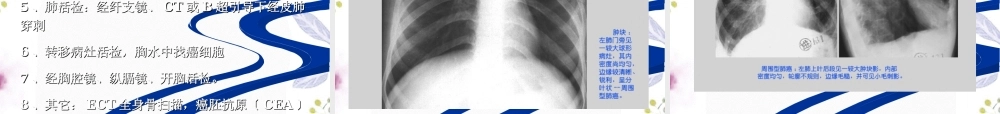

肺癌肺癌LungcancerLungcancer广东药学院外科广东药学院外科案例案例患者男性,患者男性,5252岁,因“反复咳嗽咳痰岁,因“反复咳嗽咳痰33月,痰中带血月,痰中带血22周周〞于〞于20222022年年88月月2020日入院。日入院。患者患者33月前无明显诱因出现咳嗽,为阵发性,偶有咳白色粘月前无明显诱因出现咳嗽,为阵发性,偶有咳白色粘痰,痰,22周前咳嗽加重并出现痰中带血,以晨起多见,无伴胸周前咳嗽加重并出现痰中带血,以晨起多见,无伴胸痛、发热、呼吸困难、声音嘶哑等不适。一周前于当地医院痛、发热、呼吸困难、声音嘶哑等不适。一周前于当地医院行胸部正侧位行胸部正侧位XX线检查提示右肺下叶见一占位病变,大小约线检查提示右肺下叶见一占位病变,大小约5×4cm25×4cm2,边缘毛糙,为行进一步治疗转诊我院。起病以来,边缘毛糙,为行进一步治疗转诊我院。起病以来,患者体重减轻约,患者体重减轻约4kg4kg。另患者吸烟。另患者吸烟2020余年,约余年,约2020支支//天。天。体格检查:体格检查:T36.6℃T36.6℃,,P80bpmP80bpm,,BP115/75mmHgBP115/75mmHg。。KPS80KPS80分,右锁骨上可触及一大小约分,右锁骨上可触及一大小约2cm×1.5cm2cm×1.5cm淋巴结,质中,可活动,无压痛,余浅表淋巴淋巴结,质中,可活动,无压痛,余浅表淋巴结未及明显肿大。胸廓对称无畸形,双侧呼吸动度对称,胸结未及明显肿大。胸廓对称无畸形,双侧呼吸动度对称,胸骨无压痛,双侧触觉语颤正常,未扪及胸膜摩擦感。双肺叩骨无压痛,双侧触觉语颤正常,未扪及胸膜摩擦感。双肺叩诊清音。右下肺呼吸音稍弱,余肺野呼吸音正常。心、腹无诊清音。右下肺呼吸音稍弱,余肺野呼吸音正常。心、腹无异常。异常。一、概述一、概述定义:原发于支气管粘膜或腺体的肿瘤。定义:原发于支气管粘膜或腺体的肿瘤。其发病率和死亡率都有明显增高的趋势;其发病率和死亡率都有明显增高的趋势;全世界每年有全世界每年有138138万肺癌新病例万肺癌新病例;;有有98.998.9万人死于肺癌。万人死于肺癌。WHOWHO报告肺癌居癌症死因报告肺癌居癌症死因的第一位。的第一位。男:女男:女=3-5=3-5::11三大危险因素:男性,>三大危险因素:男性,>4040岁,吸烟指数〔岁,吸烟指数〔吸烟支数吸烟支数//每天每天××吸烟年数〕>吸烟年数〕>400400支支//年年二、病因二、病因(Aetiology)(Aetiology)肺癌与以下因素有关:肺癌与以下因素有关:吸烟:是肺癌的重要危险...